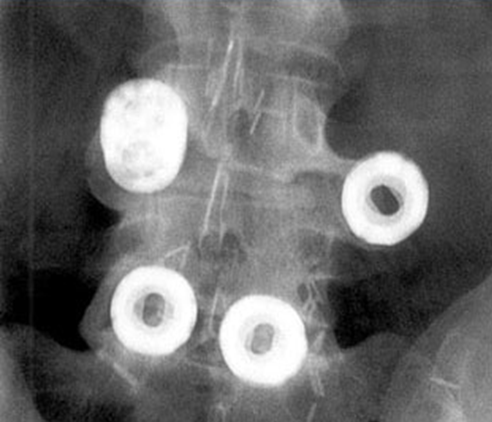

单纯ALIF技术因BAK融合器的出现而成为关注热点,其金属螺纹在植入过程中切入软骨下骨,理论上可防止沉降并促进松质骨与植骨材料接触从而达到早期融合。但不利的是,软骨下骨也可能因此受到破坏,在应力的条件下导致终板塌陷,cage陷入椎体导致椎间高度的丢失。生物力学研究发现,融合器与椎体的接触面积越大越有利于融合,对邻近节段的应力传递更少。BAK cage显然不是最完美的选择。

尽管单纯ALIF在一些研究中获得了不错的融合率,但也后期的研究中也发现不少cage出现沉降、移位(图11)。即使融合率较高,对单纯ALIF的即时稳定性仍令人担忧,往往使用前路钢板增强稳定,但钢板切迹长期摩擦大血管,可能使其变脆破裂,引起严重后果。因此,很多ALIF术后仍需要补充后路内固定,增加了手术时间、创伤和医疗费等问题。

图11 移位的BAK cage